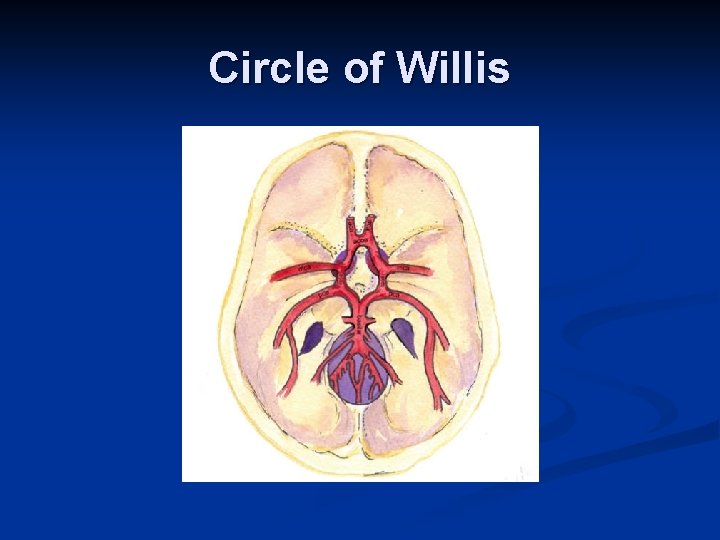

Circle of Willis (connecting the two) n n n Major collateral pathway of brain Basilar artery formed from fusion of both vertebrals Internal carotid arteries Anterior cerebral Middle cerebral Basilar artery Posterior cerebral Communicating vessels Anterior communicating artery (acoa) Posterior communicating artery (pcoa)

Circle of Willis